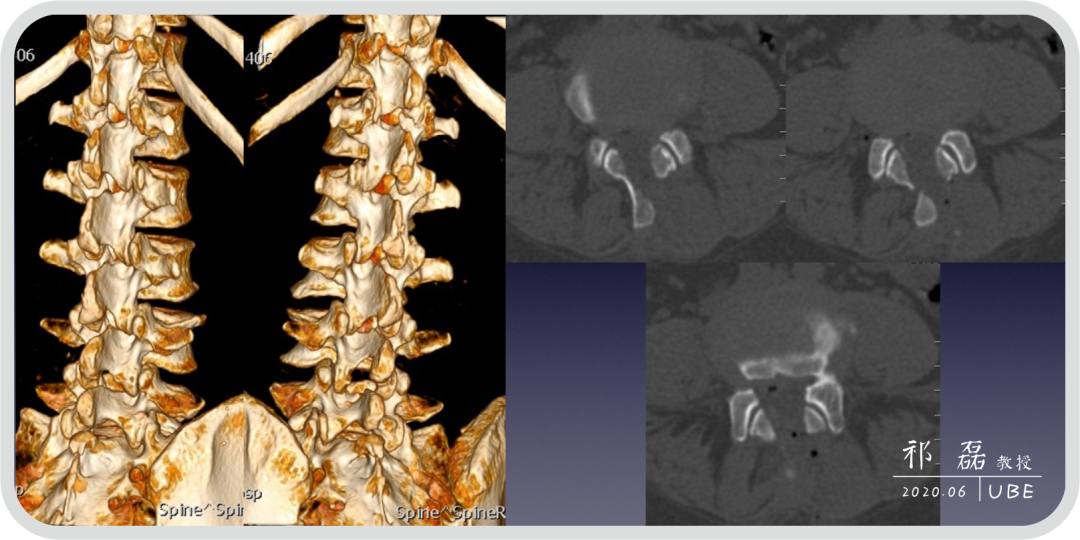

患者:吴某,女,53岁,腰痛及双下肢疼痛麻木5年余,加重1月余,间歇性跛行约200米。于近日入我院查体,下腰椎棘突及椎旁肌深压痛,双下肢感觉运动正常。双侧直腿抬高试验(-),双侧踝反射(-),入院诊断为:腰椎管狭窄症。

图2:腰椎CT